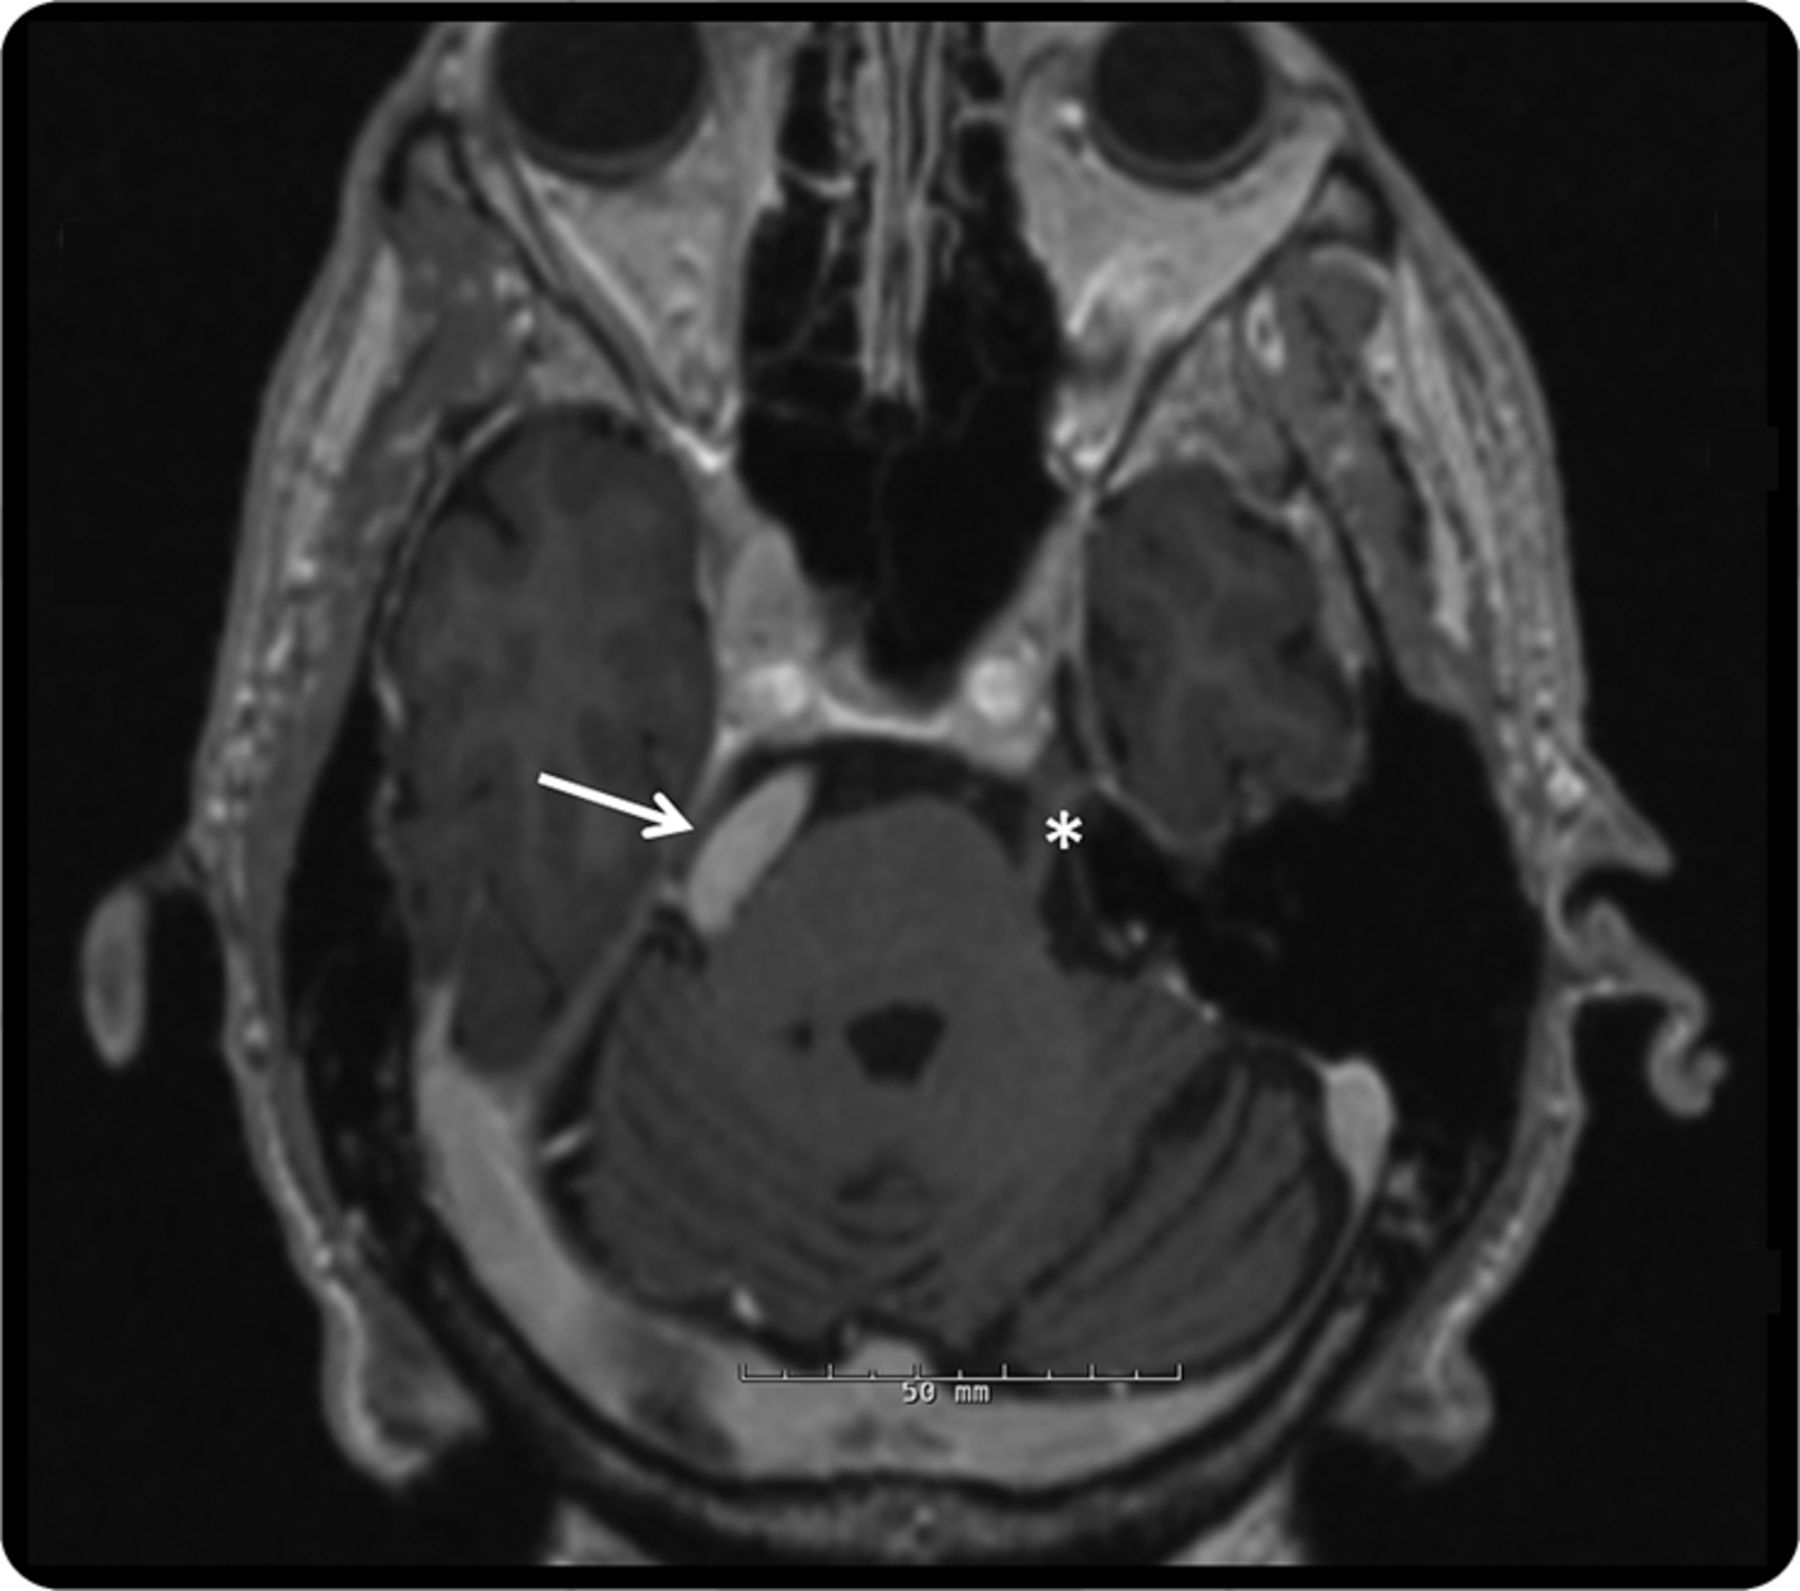

图1

大脑核磁共振,3 d magnetization-prepared快速采集、轴向视图

MRI显示dolichoectatic底动脉扭曲正确的三叉神经脑桥中期的水平(箭头所指)。作为参考,侧三叉神经显示星号。